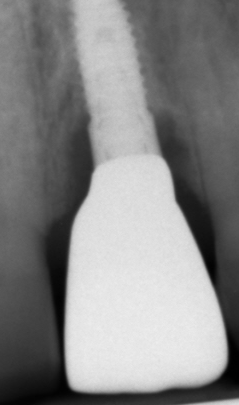

Il paziente, quando era ancora bambino, ha subito un trauma sull’incisivo centrale provocandone la necrosi e interrompendo la crescita completa della radice. Il dente è stato curato e riabilitato in modo tale da mantenerlo in arcata per più tempo possibile. A crescita completa del paziente, a causa dello stato precario dell’elemento dentario, si è proceduto con la sostituzione con un impianto osteointegrato.

PRIMA

DOPO